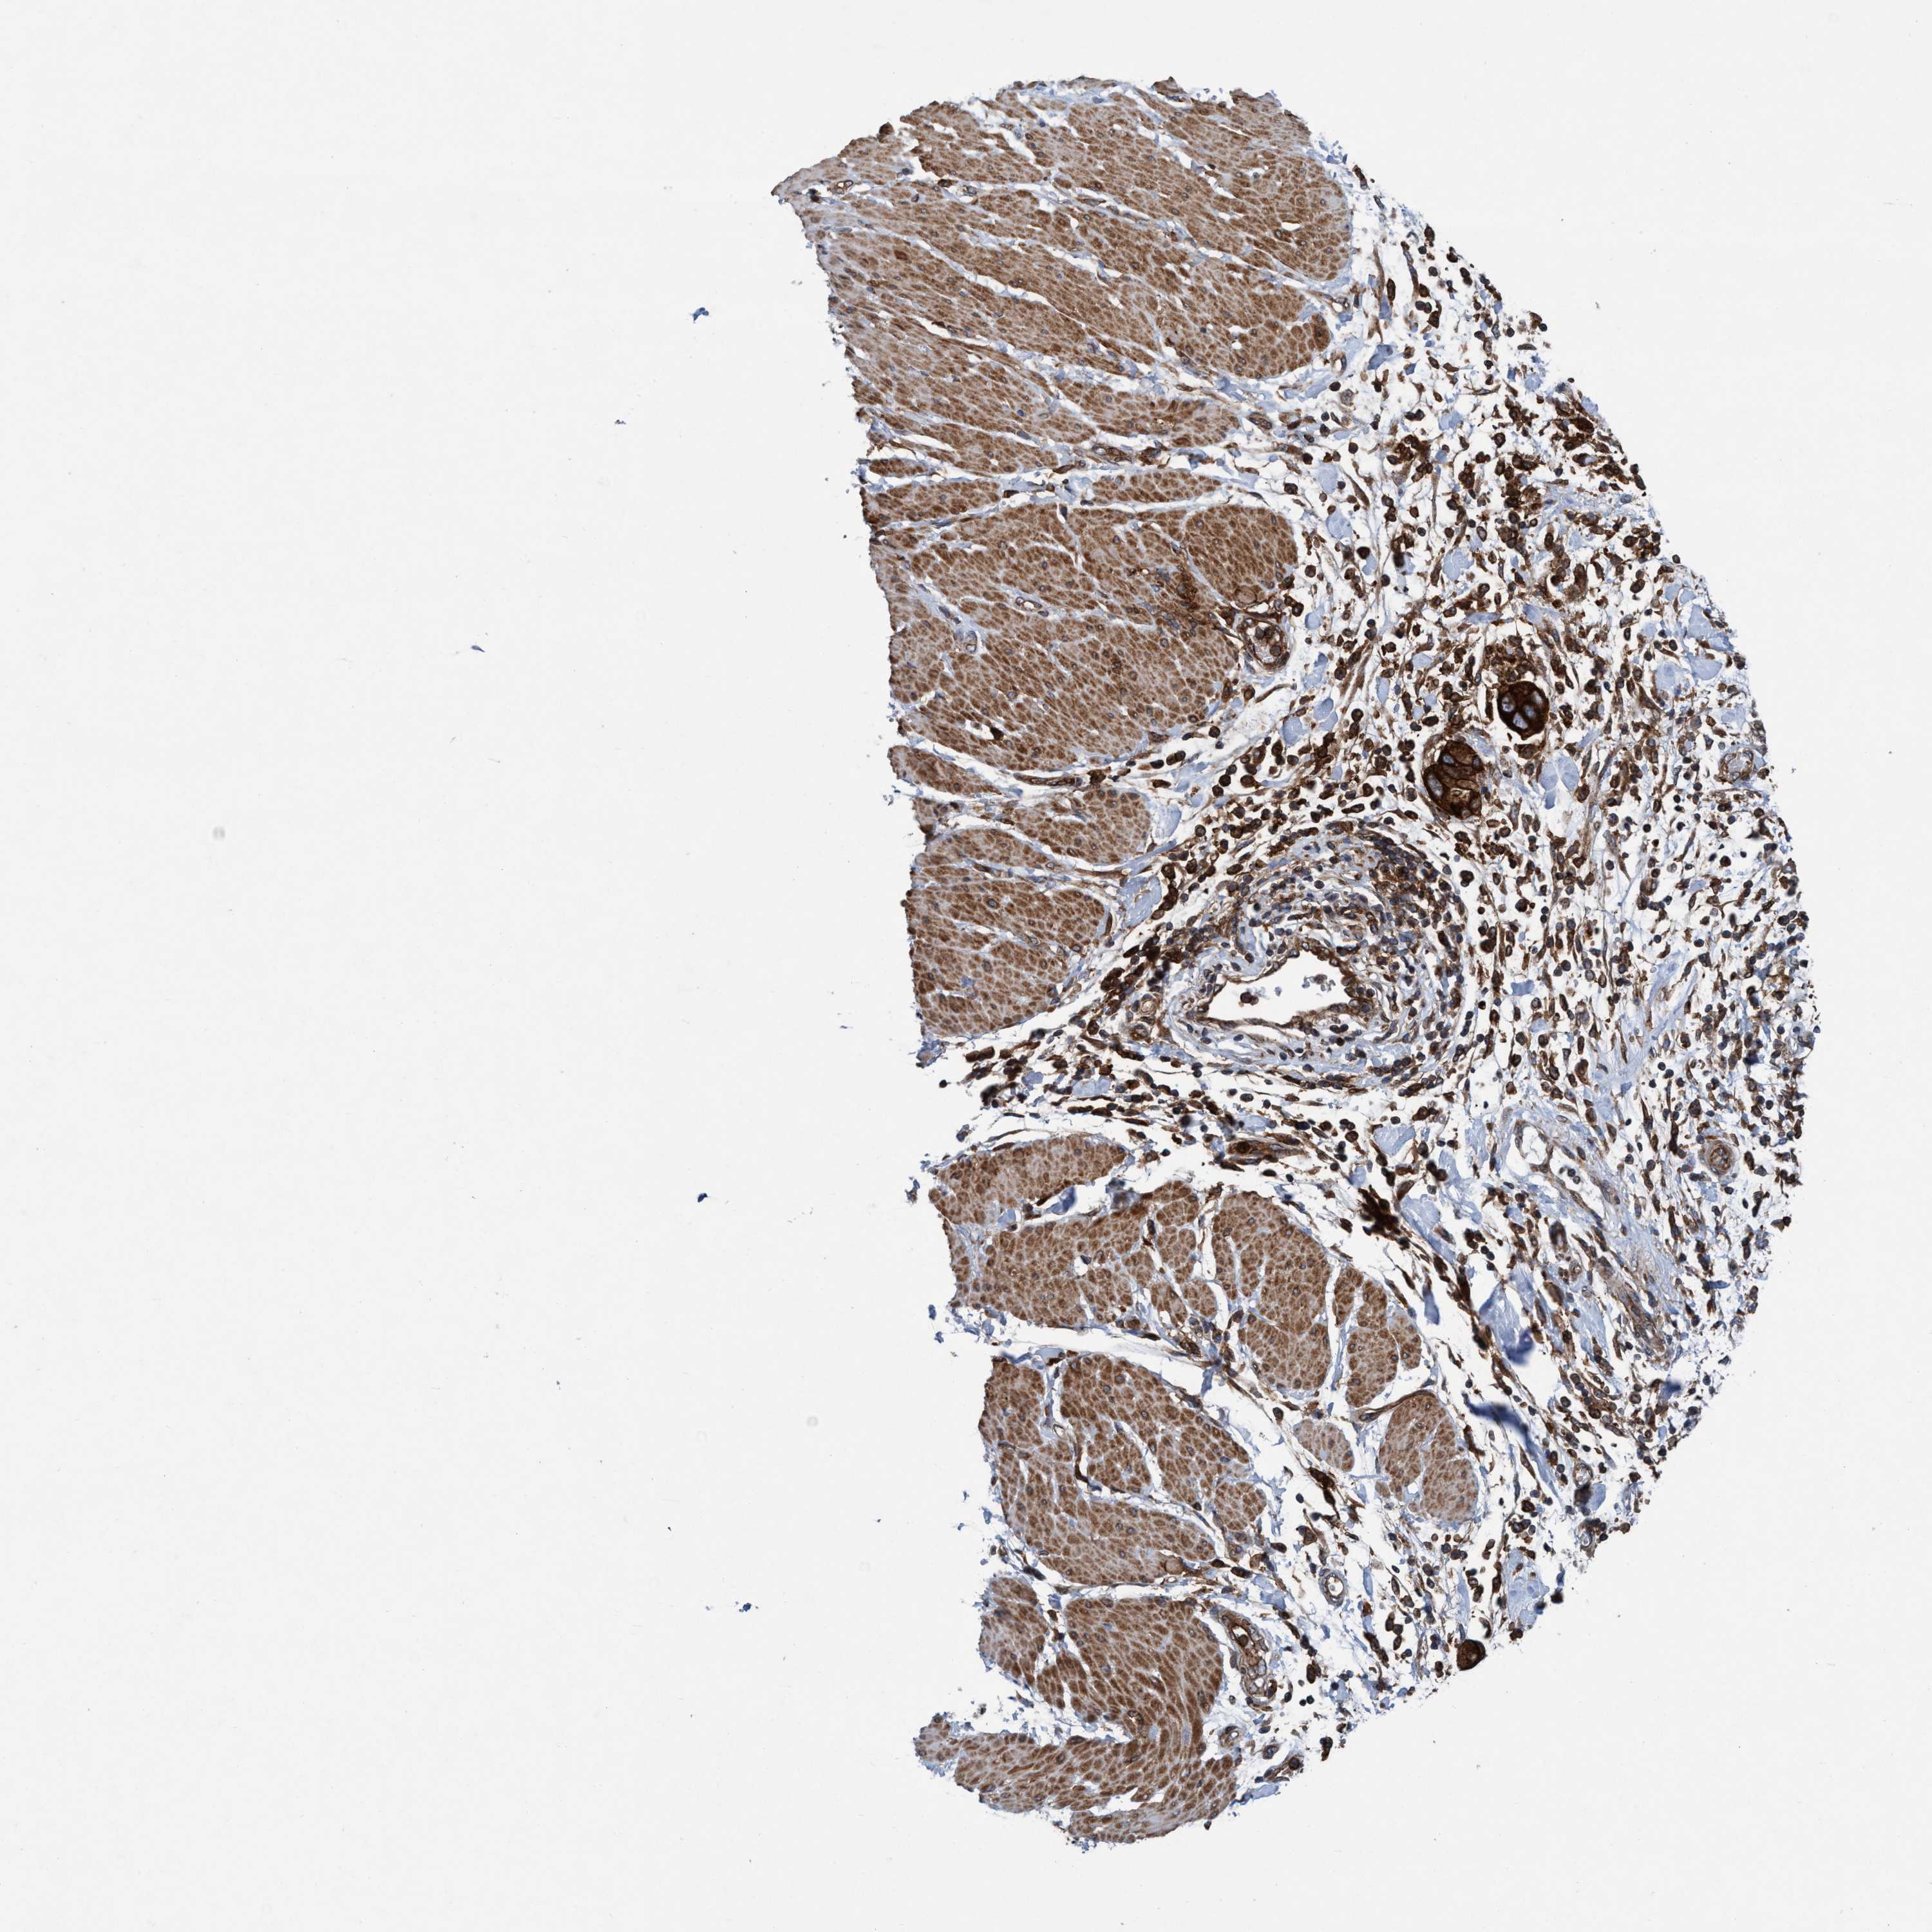

PANCREATIC CANCER - Protein expressioni

A mouse-over function shows sample information and annotation data. Click on an image to view it in a full screen mode. Samples can be filtered based on level of antibody staining by selecting one or several of the following categories: high, medium, low and not detected. The assay and annotation is described here.

Note that samples used for immunohistochemistry by the Human Protein Atlas do not correspond to samples in the TCGA dataset.

Antibody stainingi

Antibody staining in the annotated cell types in the current human tissue is reported as not detected, low, medium, or high, based on conventional immunohistochemistry profiling in selected tissues. This score is based on the combination of the staining intensity and fraction of stained cells.

Each image is clickable and will lead to virtual microscopy that enables deeper exploration of all samples and also displays staining intensity scores, fraction scores and subcellular localization as well as patient and tissue information for each sample.

Antibody HPA021451

Antibody CAB017490

Staining

High

Medium

Low

Not detected

Intensity

Strong

Moderate

Weak

Negative

Quantity

>75%

75%-25%

<25%

None

Location

Nuclear

Cytoplasmic/membranous

Cytoplasmic/membranous,nuclear

Adenocarcinoma, NOS